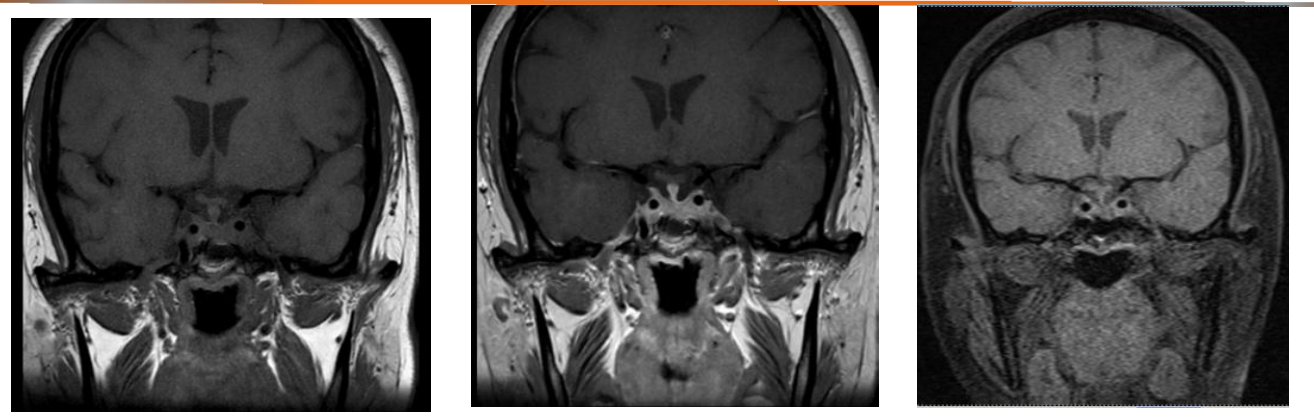

垂体MRI平扫(2024-1-5):垂体前叶饱满,提示可能存在微腺瘤;左侧额顶部见3.3×2.7 cm蛛网膜囊肿;颅骨板障增厚。垂体增强MRI(2024-1-9):右侧垂体前叶见0.9×0.5 cm异常强化影,考虑垂体瘤;视交叉未受压。

垂体核磁提示:垂体形态饱满;存在疑似垂体微腺瘤;影像改变与生化指标相一致。